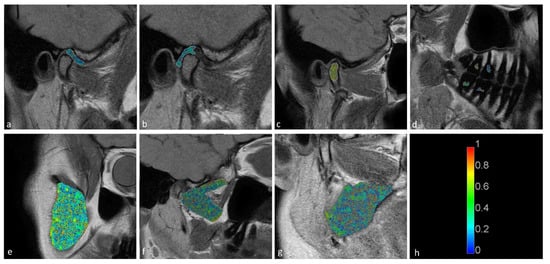

The temporomandibular disk, retrodiscal tissue, condylar bone marrow, masseter muscle, lateral pterygoid muscle medial pterygoid muscle, and dental pulp of the first and second molars were manually segmented by the dentist. The segmentation was performed twice at an interval of two months, with manual contour tracing using the VisNow Plugin Medical library [20] (Figure 1). Segmentation was performed on all slices containing the relevant structure. Due to missing molars, segmentation and further analysis of the pulp was not possible in eight joints. The intrarater reliability was assessed with the intersection-over-union measure. The average of two measurements was taken into consideration in further statistical analysis.

Statistically significant differences were observed between the displaced and nondisplaced disk groups in the retrodiscal tissue short T2 component (p < 0.0001) short fraction (p = 0.0050) and long fraction (p = 0.0049), the medial pterygoid muscle short T2 component (p = 0.0025) as well as the bone marrow long T2 component (p = 0.0030) and short T2 component (p = 0.0116), indicating the relationship between disk displacement and quantitative MRI features of stomatognathic anatomical structures. The pulp short T2 component showed a trend toward statistical significance (0.0125 < p < 0.0500). Sample T2 maps are presented in Figure 2 and Figure 3. Short and long fraction components are presented in Figure 4 and Figure 5, respectively. The Shapiro–Wilk test confirmed normality in all comparisons.

Figure 1. Samples of stomatognathic anatomical structure segmentation for the (a) disk; (b) retrodiscal tissue; (c) bone marrow of the condyloid process; (d) pulp; (e) m. masseter; (f) m. pterygoideus lateralis; and (g) m. pterygoideus medialis.